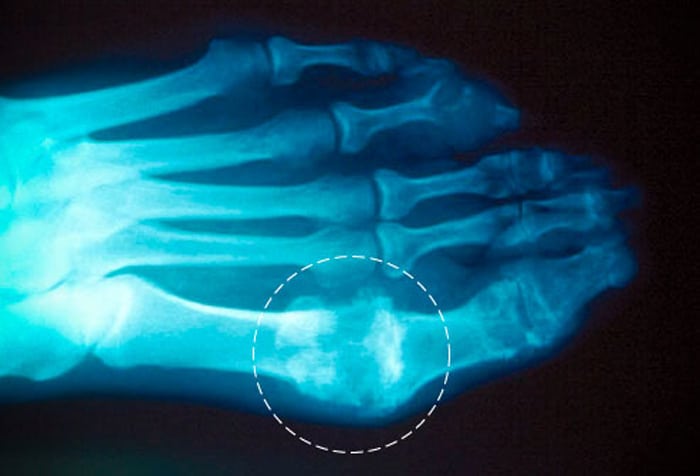

- болезненные ощущения и отечность первого плюснефалангового сустава;

- одностороннее поражение свода стопы;

- обнаружение субкортикальных кист без эрозии при проведении рентгенографии.

Рентгенологическое исследование наиболее информативно при рецидивирующем полиартрите. На полученных изображениях в эпифизарных областях обнаруживаются светлые фрагменты. При подагре высокой степени тяжести визуализируются участки костных эпифизов с деструктивными изменениями и отложенными солями — уратами.